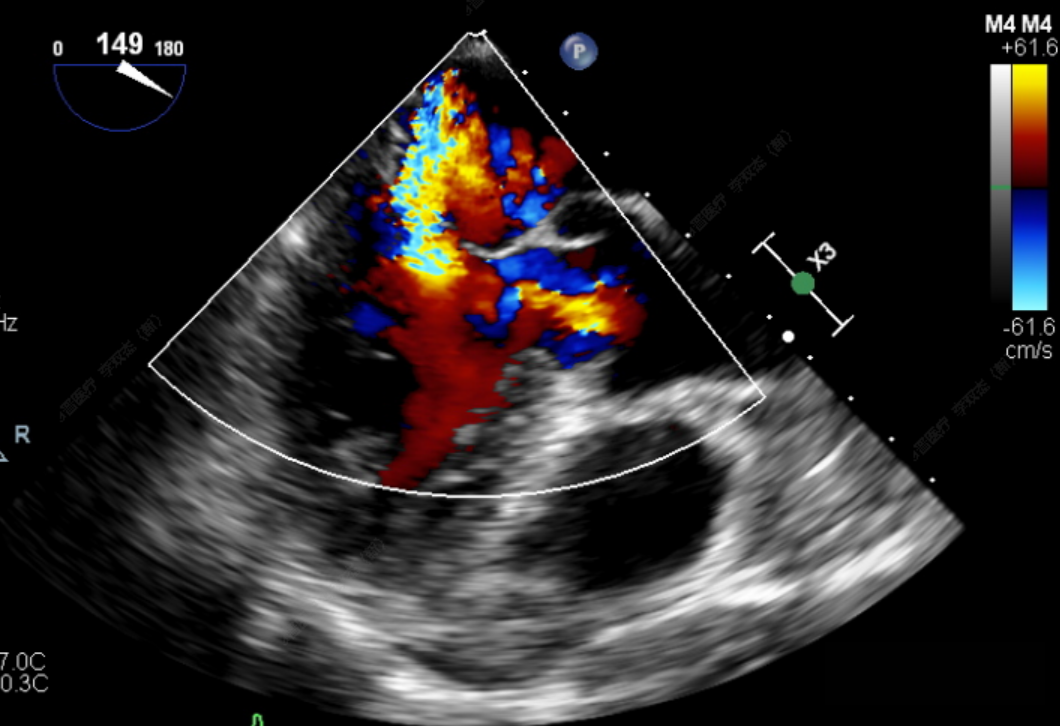

此次手术患者均为高龄、且外科高危的器质性二尖瓣反流,反流病变区域遍及前后瓣叶(一区、二区、三区),复杂及多样性的病变状况大大增加了手术的操作难度性,是对术者与器械稳定及有效性的巨大考验。术中,器械经股静脉穿刺房间隔,通过输送系统送入患者左心房,到达二尖瓣膜反流处,在经食道超声及DSA引导下,通过反复评估脱垂范围、抓捕位置、反流程度,确保细致操作、精准夹合、释放。术后即刻,患者反流显著减小,左房压下降,血流动力学改善明显,短暂过渡后,首位患者安返病房。导管室内,华西心脏瓣膜团队仍严阵以待,为之后两例手术做准备,经过团队之间紧密配合,三台手术均顺利完成。